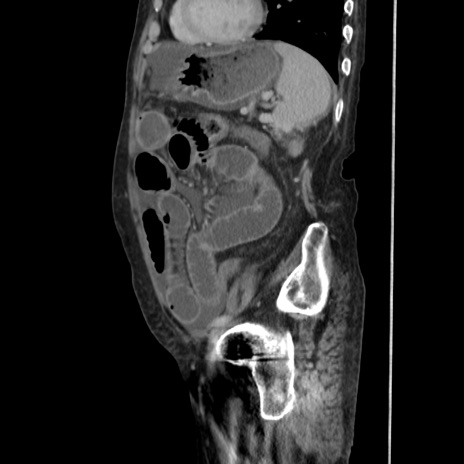

症例31(矢状断像)

【症例】80歳代 女性

【主訴】腹部膨満感

【現病歴】他院にて肝硬変にてフォロー中。1週間前から便秘、腹部膨満感、臍部腫瘤あり受診となる。

【既往歴】肝硬変

【身体所見】腹部膨隆あり、皮膚変化なし、疼痛なし。

【データ】WBC 4600、CRP 0.25